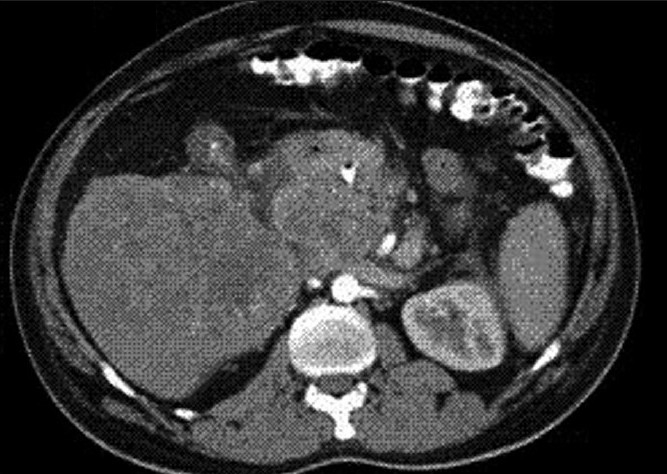

Physical examination revealed severe icterus and liver enlargement up to 5 cm below the right costal margin. The liver was hard and nontender. Ultrasonography (USG) and computed tomography (CT scan) revealed a large right and caudate lobe liver mass involving the gallbladder and common bile duct, with intrahepatic biliary radical (IHBR) dilatation, favoring the diagnosis of carcinoma gall-bladder with liver metastasis [Figures [Figures11 and and22].

| Figure 2 CT abdomen (Transverse section) showing a large caudate lobe liver mass involving the gall bladder and common bile duct at porta with IHBR dilatation